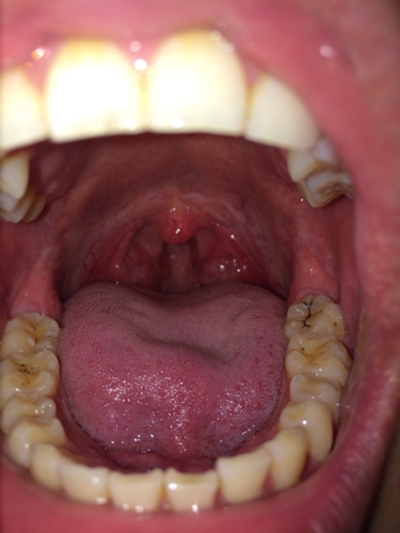

口腔黏膜病圖片

口腔念珠菌感染 (47)